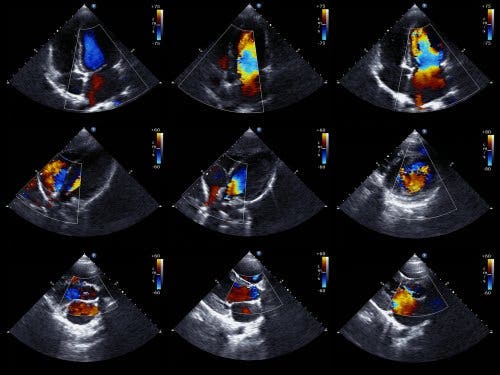

Echokardiogram- wysięk w osierdziu

Obrazy z echokardiogramu, to jedna z miar do wykrywania wysięku w osierdziu. Ta technika jest jedną z najczęściej stosowanych w diagnozowaniu chorób serca i najczęściej stosowaną metodą ilościowego określania nagromadzonej w osierdziu cieczy.

Echokardiogram jest zazwyczaj najpopularniejszym preferowanym badaniem do wykrywania wysięku osierdziowego. Nazywa się go również echokardiografią lub USG serca i jest to badanie, które pozwala lekarzom zobaczyć całą strukturę serca i zbadać jego zdolność do prawidłowego pompowania krwi.

Echokardiogram dopplerowski pozwala również lekarzom określić dokładną prędkość przepływu krwi z serca. Z technicznego punktu widzenia dwuwymiarowy echokardiogram w trybie M jest idealną techniką do diagnozowania, oceny ilościowej i monitorowania wysięku osierdziowego.

Badanie to umożliwia w sposób nieinwazyjny ocenę anatomii serca, a także ocenę ruchu mięśnia sercowego i zastawek oraz przepływ krwi w obrębie przedsionków i komór serca. Ocenia też duże naczynia sercowe (aorta, żyły główne, tętnica i żyły płucne) i naczynia wieńcowe.

Stwierdzenie braku echa pomiędzy nasierdziem a bocznym osierdziem pozwala lekarzom na rozpoznanie wysięku osierdziowego. Następnie kardiolog określa wielkość wysięku na podstawie ilości miejsca między dwiema warstwami osierdzia.